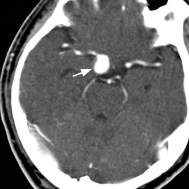

未破裂的脑动脉瘤的CT典型表现 破裂的脑动脉瘤 CT表现(SAH)